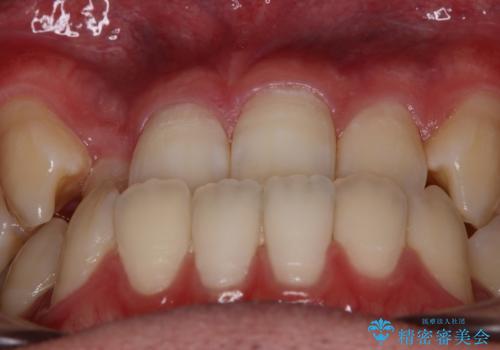

心配していた歯肉退縮も起こらず、前歯の噛み合わせと歯並びが綺麗に改善されました。

期間も1年2ヶ月と短期間で終了することができ、とても満足度の高い治療になりました。